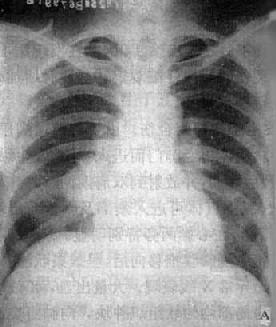

由于病灶系多次血行播散所形成,故X线表现为大小不一、密度不同、分布不均的多种性质的症灶(图3-1-23)。小者如粟粒,大者可为较大的结节状,主要分布于两肺上、中野,下野较少。早期播散的症灶可能已经钙化,而近期播散的病灶仍为增殖性或渗出性。本型结核发展较慢,经治疗新鲜病灶可以吸收,陈旧病灶多以纤维钙化而愈合。恶化时病灶可融合并形成空洞或逐渐转为慢性纤维空洞型肺结核。

图3-1-23 慢性血行播散型肺结核

两肺野布满大小不一、密度不同、分布不均的病灶,

下野较少,膈位置低而平